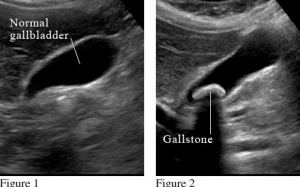

Sỏi mật ảnh hưởng đến 10 - 15% người Mỹ và khoảng 800.000 người mỗi năm phải phẫu thậu cắt bỏ túi mật vì có sỏi. Biện pháp hiệu quả để phòng ngừa sỏi mật là thay đổi chế...